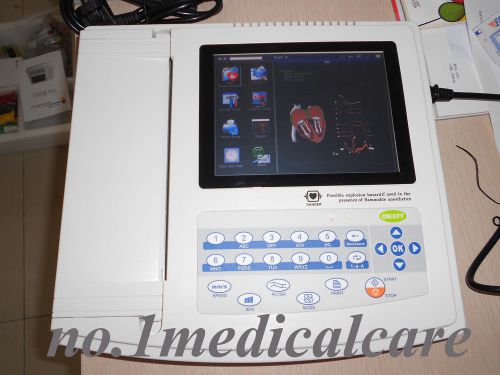

CONTEC Professional Portable Digital ECG Machine, ECG1200G, Factory direct sale